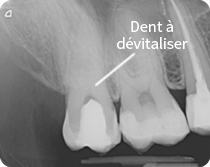

Dans le cas où les tissus internes de la dent ont été attaqués, sont malades ou encore que les tissus qui entourent la racine soient abimés, il est nécessaire d’entamer un traitement endodontique (ou un soin canalaire, communément appelé dévitalisation).

Dans le cas où un traitement endodontique soit nécessaire, il doit être effectué dans les règles de l’art pour pouvoir être efficace et ne pas créer de problèmes à l’avenir. Dans les CLINICHE DENTAL QUALITY nous intervenons à l’aide de:

- l’éviction du nerf dentaire malade situé à l’intérieur de la dent ainsi que dans les racines;

- nettoyage et mis en forme des canaux à l’aide d’instruments spéciaux

- l’étanchéité avec une obturation permanente.

A la fin d’un traitement correctement réalisé, la dent reprendra les mêmes fonctions d’une dent entière.